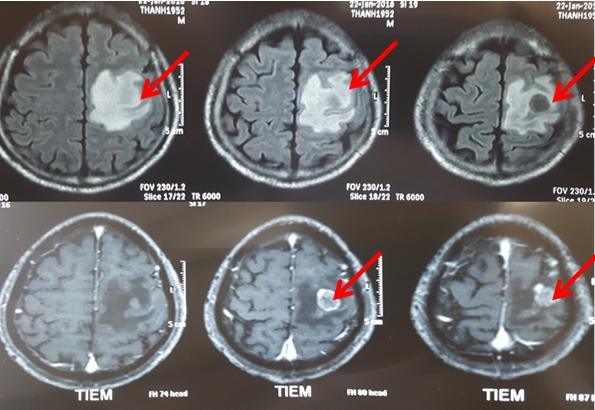

-       Chụp cộng hưởng từ sọ não: Thấy tổn thương não dạng u di căn tại thùy đỉnh thái dương trái kích thước 2,1x2cm, ngấm thuốc mạnh, phù não rộng xung quanh.

Hình 1: Hình ảnh khối u di căn trên phim cộng hưởng từ sọ não